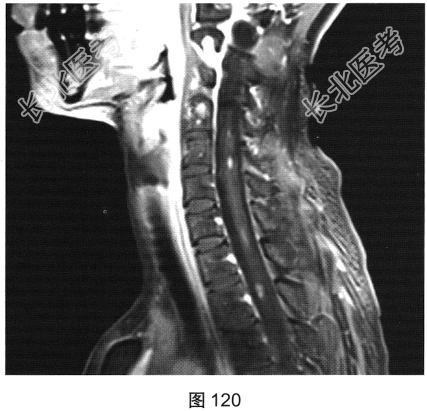

- 多项选择题2.[提示]患者行脊柱MRI检查,如图115~图120所示。患者MRI检查可见哪些阳性影像学表现( )

A、T2WI示颈髓和胸髓病灶呈高信号

B、增强扫描颈髓病灶多发斑片状强化

C、横断面增强扫描脊髓侧索病灶强化

F、T1WI示颈髓病灶呈等信号